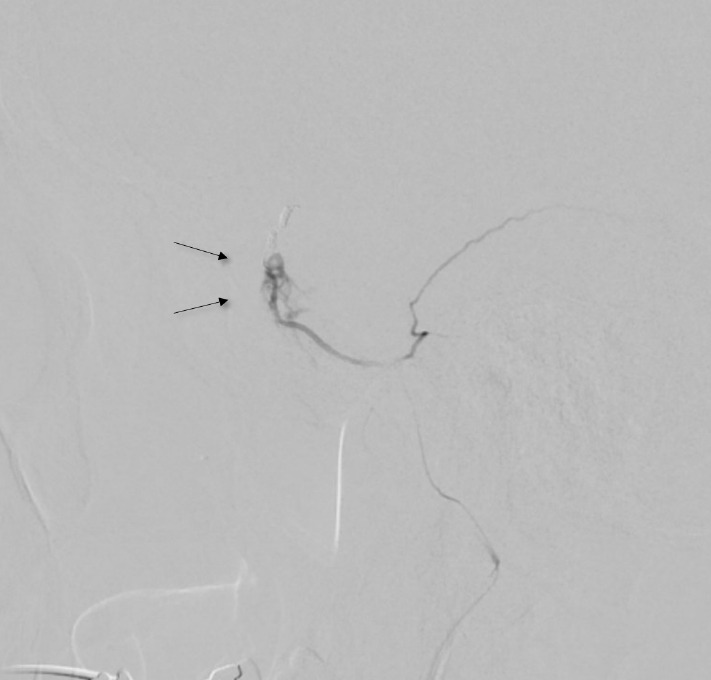

We present a case of a meningo-meningeal arteriovenous fistula (MMAVF) discovered immediately following middle meningeal artery (MMA) microparticle embolization for the treatment of an acute subdural hematoma (SDH). An elderly patient presented with an SDH found during stroke workup. MMA embolization was elected due to his need for therapeutic anticoagulation. During the procedure, multiple MMAVFs appeared after microparticle embolization of the distal MMA branches. We aborted further microparticle embolization and performed coil embolization of the MMA trunk with cessation of flow. No clinical complication was noted postoperatively and no post-procedure hemorrhage was seen. Review of literature suggests that this phenomenon may be associated with microparticle embolization. We hypothesize the cause to be vessel rupture due to barotrauma during manual injection via the microcatheter. As MMA embolization becomes more common, this complication may become more recognized.